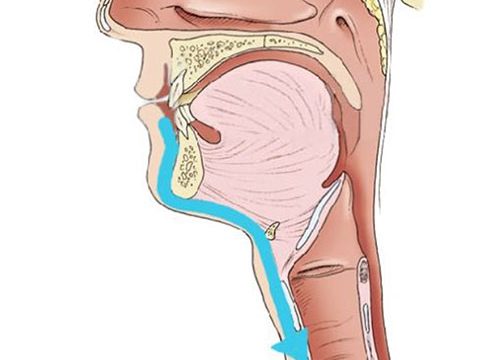

Dla Pań, które nie chcą mieć blizny na szyi po operacji tarczycy oferujemy operację tarczycy techniką endoskopowego wycięcia tarczycy z dostępu przez przedsionek jamy ustnej (ang.TransOral Endoscopic Thyroidectomy by Vestibular Approach – TOETVA) przy użyciu neuromonitora. W technice TOETVA dostęp operacyjny do tarczycy następuje nie jak w klasycznej chirurgii tarczycy poprzez wykonanie cięcia w dolnej części szyi lecz małoinwazyjnymi metodami endoskopowymi przez przedsionek jamy ustnej po założeniu trzech trokarów: jednego o średnicy 10mm oraz dwóch o średnicy 5mm, co pozwala na uniknięcie cięcia na skórze szyi i uzyskanie dobrego efektu kosmetycznego po operacji wynikającego z braku blizny na skórze szyi. Niewielkie rany po trokarach w obrębie przedsionka jamy ustnej szybko się goją z dobrym efektem kosmetycznym. Zabiegi operacyjne realizuje prof. Marcin Barczyński wraz z zespołem.